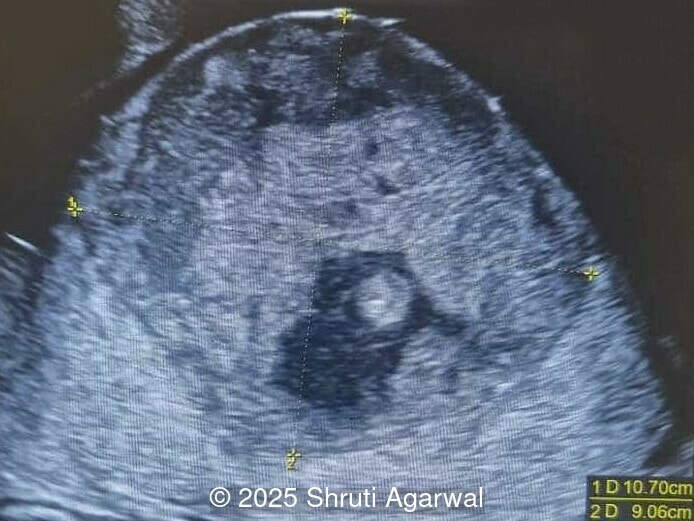

27-year-old primigravid woman presented for ultrasound evaluation at 27 weeks gestation. There was no significant family history or drug exposure during pregnancy. The following findings were observed:

We present a case of fetal anemia due to a giant chorangioma.

• Image 1,2: Large placental tumor is identified with internal vascularity

Prenatal diagnosis depends on ultrasound, however, chorangioma can cause an increase in maternal serum alpha-fetoprotein [3]. Ultrasound examination reveals a hypo- or hyperechoic, well-circumscribed mass, which is usually located underneath the chorionic plate near the umbilical cord insertion, and often protrudes into the amniotic cavity. Color Doppler demonstrates large vascular channels around and within the tumor [6,9]. In cases of giant chorangiomas, echocardiography should be performed to assess cardiac function and measure fetal middle cerebral artery peak systolic velocity for diagnosis of fetal anemia. Regular ultrasounds with Doppler studies are used to monitor tumor size, fetal growth, amniotic fluid volume, and signs of fetal anemia or heart failure. The frequency of exams is based on tumor size and associated complications. With small tumors, assessment may occur every 3-4 weeks, whereas in large tumors, the ultrasound scan may be done every 1-2 weeks [3]. These regular assessments can diagnose conditions that require intervention, such as polyhydramnios, hydrops, or hemolytic anemia.